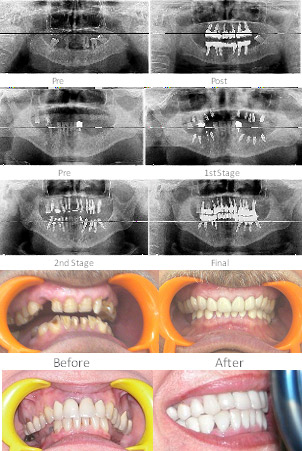

Correction of teeth alignment done without braces. Teeth just walked naturally into their designated places. This science is also called as “Epigenetics”. No braces wonder. Facial features also improve substantially by the treatment. The model here later got veneers for Whitening etc.

A few full mouth implants case done at ADCRI (Zental Dental).